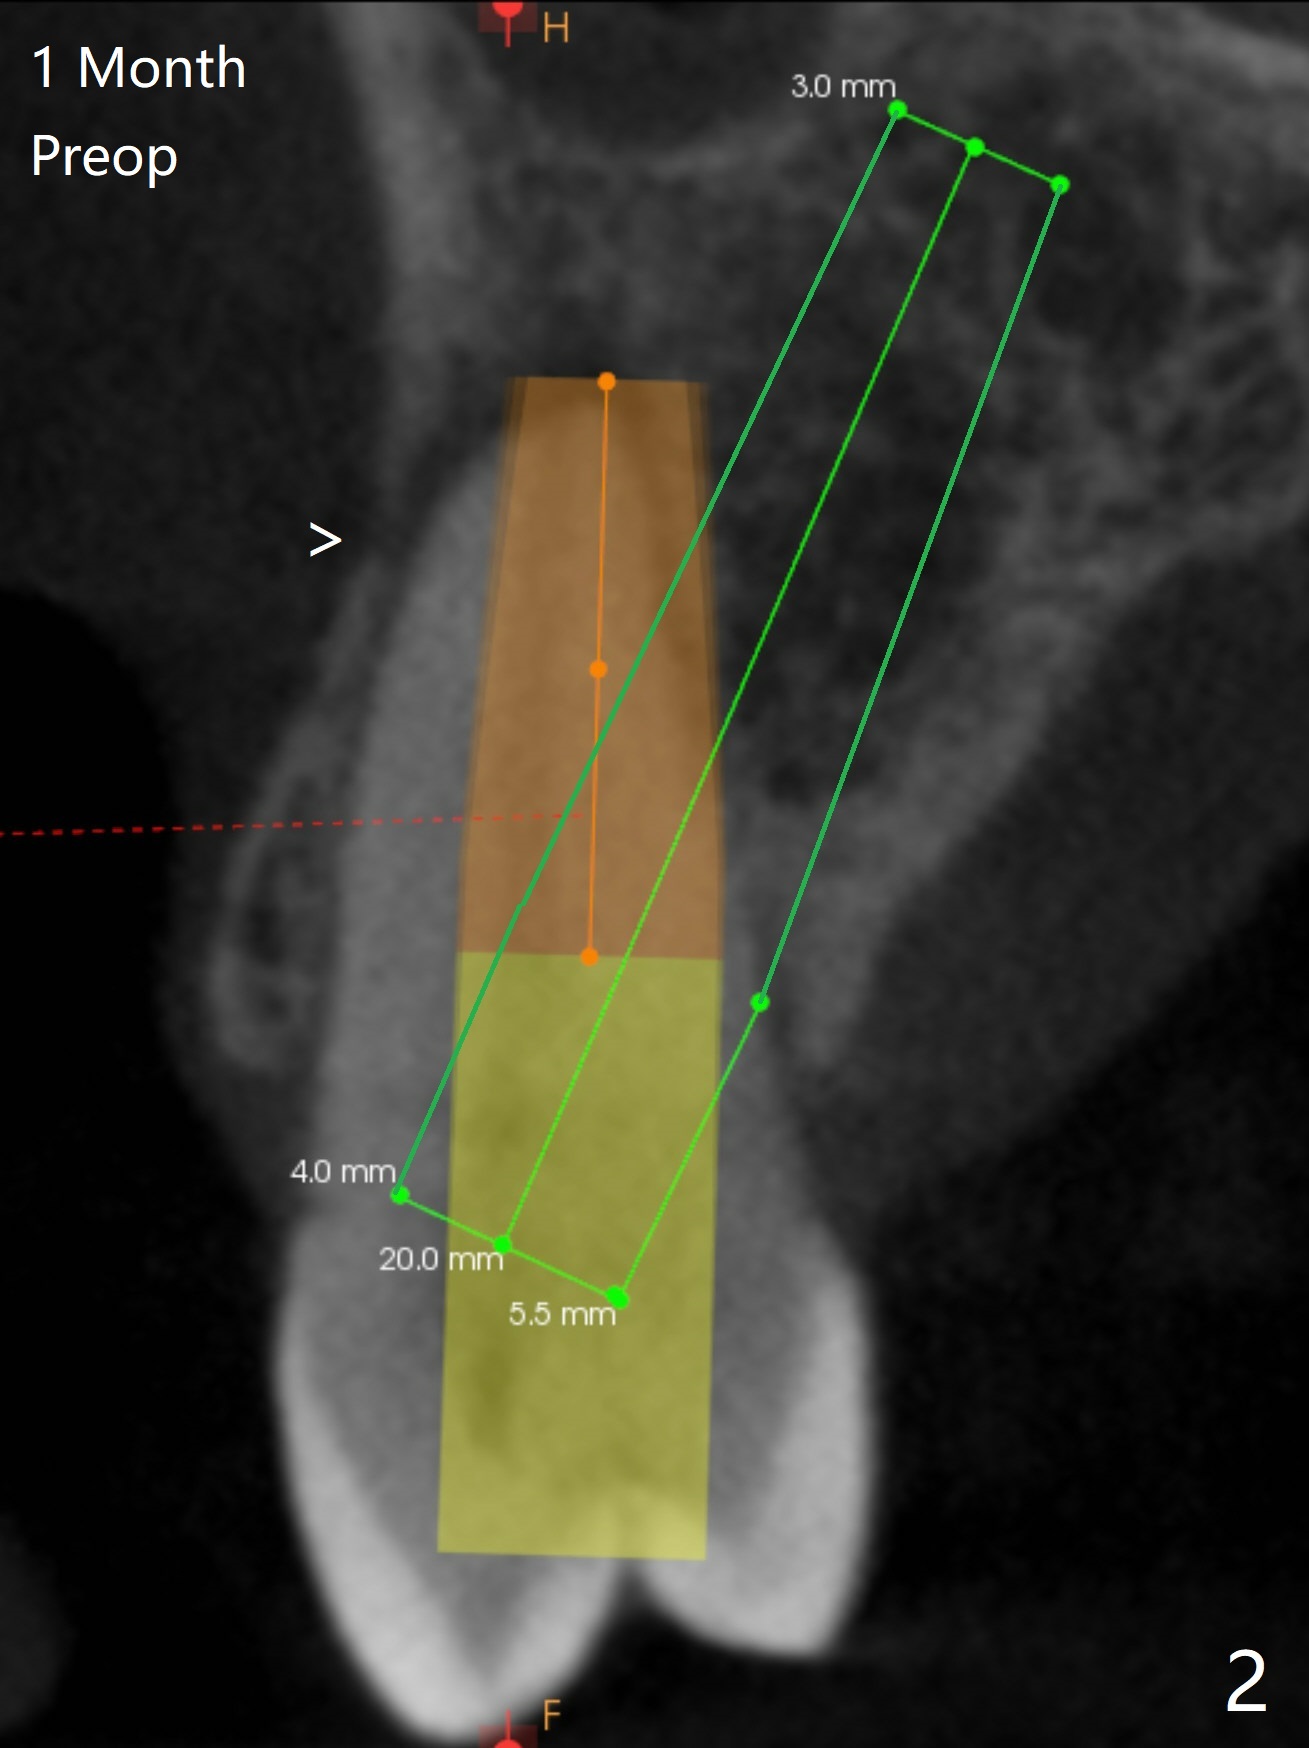

一个月前12号牙仅有隐裂(与术前即刻(图一)对比),当时CT显示轻度颊侧根尖缺损(图二:>)。拔牙后颊侧根尖没有骨板,所以钻洞偏腭侧(图三);完成最后钻头(3毫米)后,后者保持原位,先在颊侧根尖植骨,然后取出钻头,植入植体(图四),放置基台后,在后两者周围再置入骨粉,最后制作临时牙冠固定骨粉。由于骨质密度低(图二;术中钻洞容易),选择20毫米植体,扭力50Ncm。